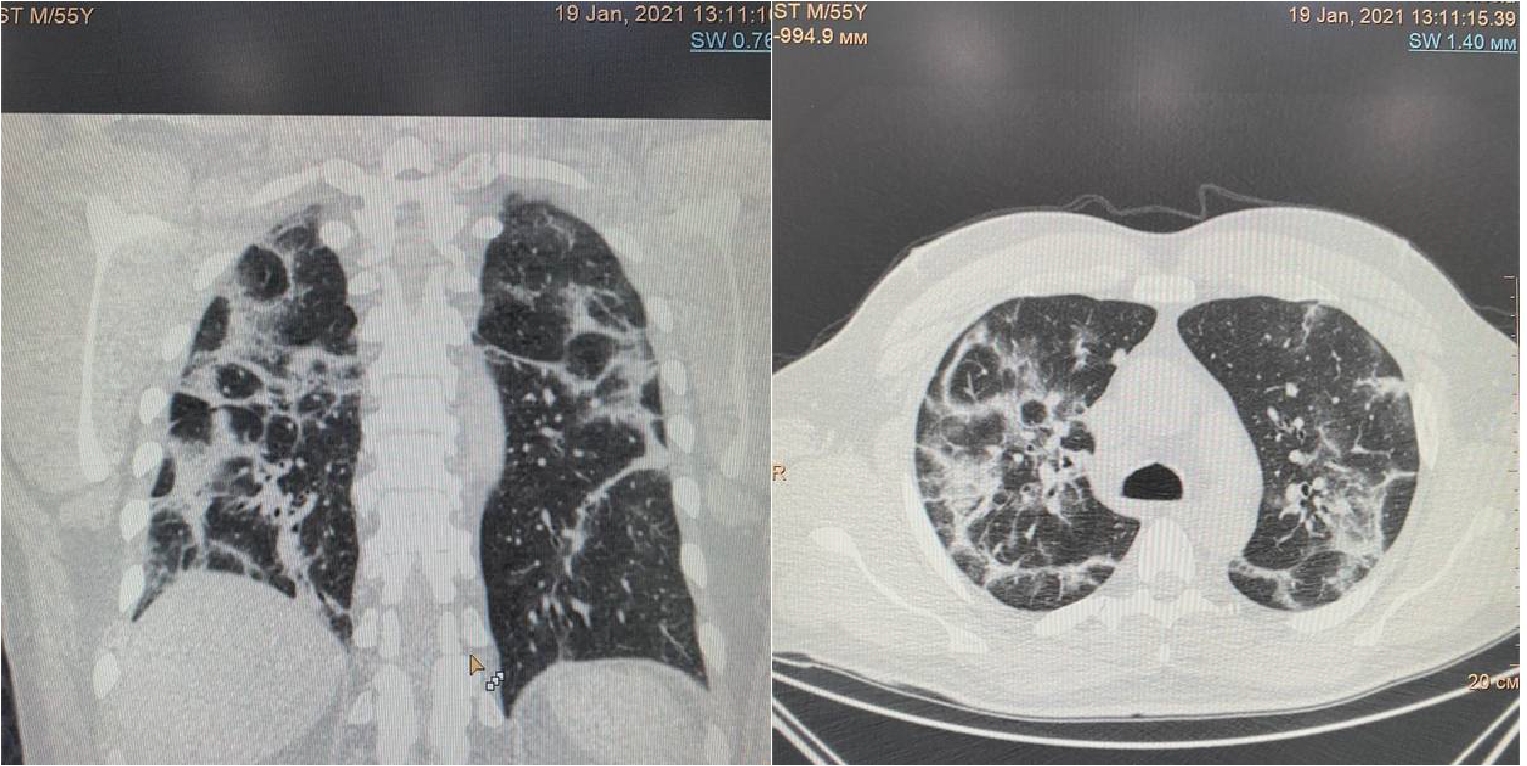

Рисунок 2. МСКТ органов грудной клетки – признаки двусторонней полисегментарной интерстициальной пневмонии (объем поражения 40%, КТ-2)

На 4-е сутки госпитализации выявлено ухудшение клинического статуса (снижение SpO2 до 93%, температура тела более 38 0С), отрицательная динамика по МСКТ (объем поражения 28%, КТ-2, в связи с чем к лечению добавлен олокизумаб однократно, без отчетливого клинического эффекта. На 7-е сутки госпитализации МСКТ выявила дальнейшее прогрессирование поражения легких (объем поражения 40%, КТ-2 (рис.2) на фоне сохранения умеренно выраженного кашля (со скудной мокротой), нарастания дыхательной недостаточности (SpO2 85-88% без инсуффляции кислорода). Больной переведен в отделение анестезиологии и реанимации, где находился в течение 3 суток, лечение включало преднизолон 480 мг/сут (начальная доза), противокашлевый препарат центрального действия (бутамират), проведен плазмоферез (аппарат Fenwal; инфузия плазмы - 2440 мл, эксфузия плазмы - 1430 мл) с введением антиковидной плазмы (270 мл).